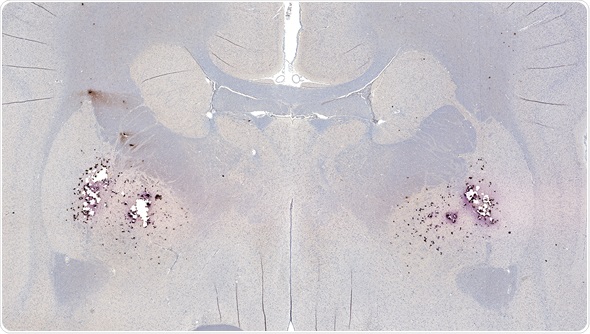

Amyloid plaques consist of dense, mostly insoluble clumps in the spaces between the nerve cells in the brain tissue. The plaques are made up of beta-amyloid, which is a protein peptide or fragment that appears to have toxic effects on the function of the surrounding brain cells.

Neurofibrillary tangles are another hallmark characteristic of the brain tissue associated with Alzheimer’s disease. They involve the twisting of tau protein threads of the nerve cells in the brain tissue.

The difference between the plaques and tangles lies in their structure and effect on the nerve cells in the brain tissues. Amyloid plaques are clusters that form in the spaces between the nerve cells, whereas the neurofibrillary tangles are a knot of the brain cells. Both are thought to interfere with the nervous messages within the brain tissue.